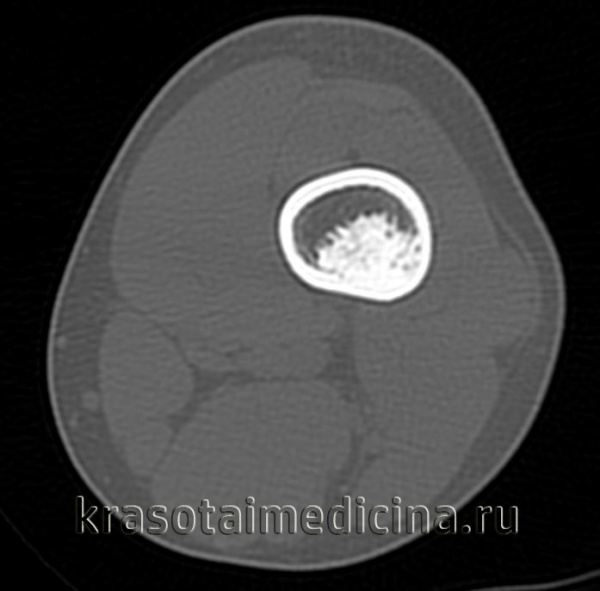

КТ левого бедра. Объемное образование (оссифицированная энхондрома) в нижней трети диафиза бедренной кости.

Хондрома

Доброкачественная опухоль кости, развивающаяся из хрящевой ткани. Может быть одиночной либо множественной. Локализуется хондрома в костях стопы и кисти, реже – в ребрах и трубчатых костях. Может располагаться в костномозговом канале (энхондрома) или по наружной поверхности костей (экхондрома). Озлокачествляется в 5-8% случаев. Обычно течет бессимптомно, возможны неинтенсивные боли. На рентгеновских снимках определяется округлый либо овальный очаг деструкции с четкими контурами. Отмечается неравномерное расширение кости, у детей возможна деформация и отставание роста сегмента конечности. Лечение хирургическое: резекция (при необходимости с эндопротезированием или костной пластикой), при поражении костей стопы и кисти иногда требуется ампутация пальцев. Прогноз благоприятный.